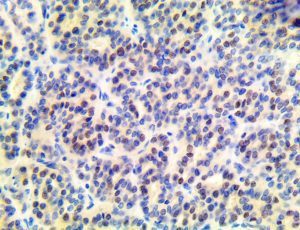

It is the ICU physician who is most likely to witness one of the deadliest manifestations of the abnormal immunological response, the cytokine storm syndrome (CSS). This response is also referred to by some as the cytokine release syndrome (CRS). CSS is characterized by continuous activation and expansion of macrophage and lymphocyte populations, which secrete large amounts of cytokines, causing the cytokine storm. This massive cytokine release is akin to hemophagocytic lymphohistiocytosis (HLH) disease, a syndrome characterized by initial unchecked and persistent activation of cytotoxic T lymphocytes and NK cells.

Clinical and laboratory manifestations of HLH include fever, enlarged liver and/or spleen, neurologic dysfunction, coagulopathy, liver dysfunction, cytopenias (i.e., low levels of erythrocytes, leukocytes, and/or platelets), hypertriglyceridemia, hyperferritinemia, hemophagocytosis, and eventually diminished NK cell activity as the immune system becomes progressively paralyzed. HLH can be familial (primary HLH) or secondary to another disease process (sHLH), such as rheumatic disease, in which it is referred to as macrophage activation syndrome (MAS, characterized by elevated ferritin).